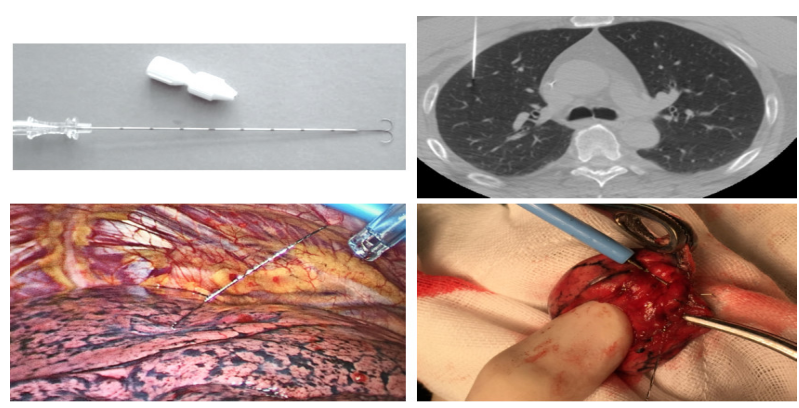

2、肺结节的术前术中定位方式

术前定位有CT 引导下经皮肺穿刺亚甲蓝注射、放置微弹簧圈、Hook-Wire 定位、放射性示踪剂注射;经电磁导航支气管镜引导注入染色标志物或微弹簧圈等(费用贵)。术中定位有术中胸腔镜 B 超探头定位、术中CT定位。但是术前定位存在许多缺点如定位不准确、移位、出现血气胸等并发症,尚需密切注意并需进一步研究完善。

图八 CT引导下钩针(Hookwire)定位